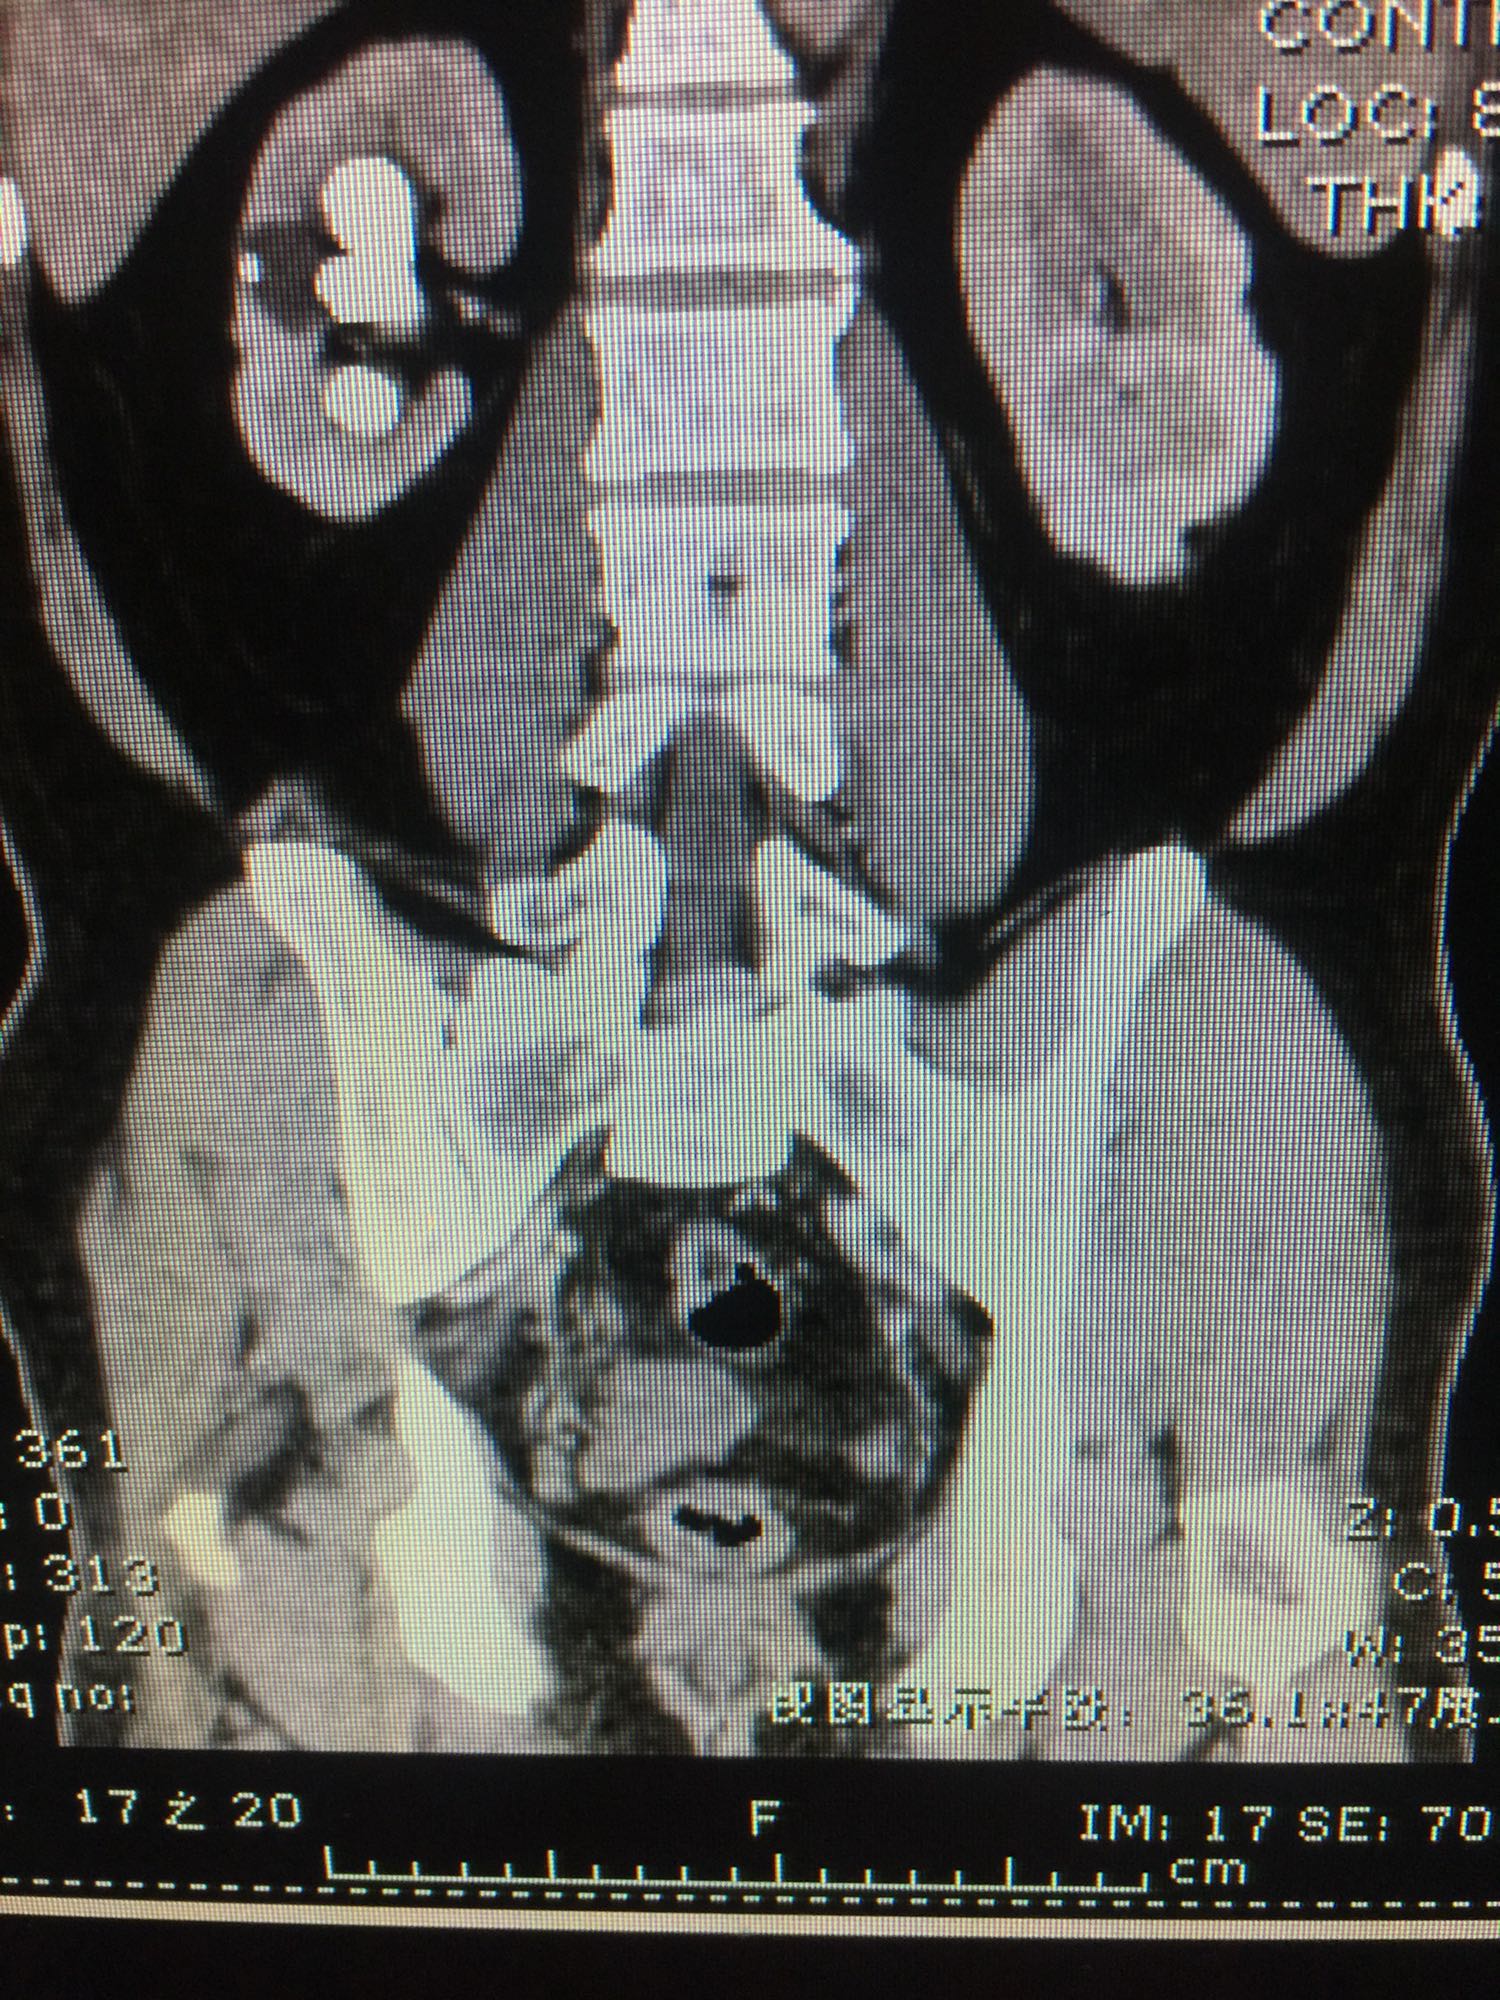

查体:双肾区无叩压痛,膀胱区无叩压痛,无叩浊,前列腺二度,质地中等,无压痛,无结节。CTU提示右肾铸型结石。ECTL 40,R14.5

右肾铸型结石 予以经皮肾碎石治疗,术后复查平片未见结石残留。